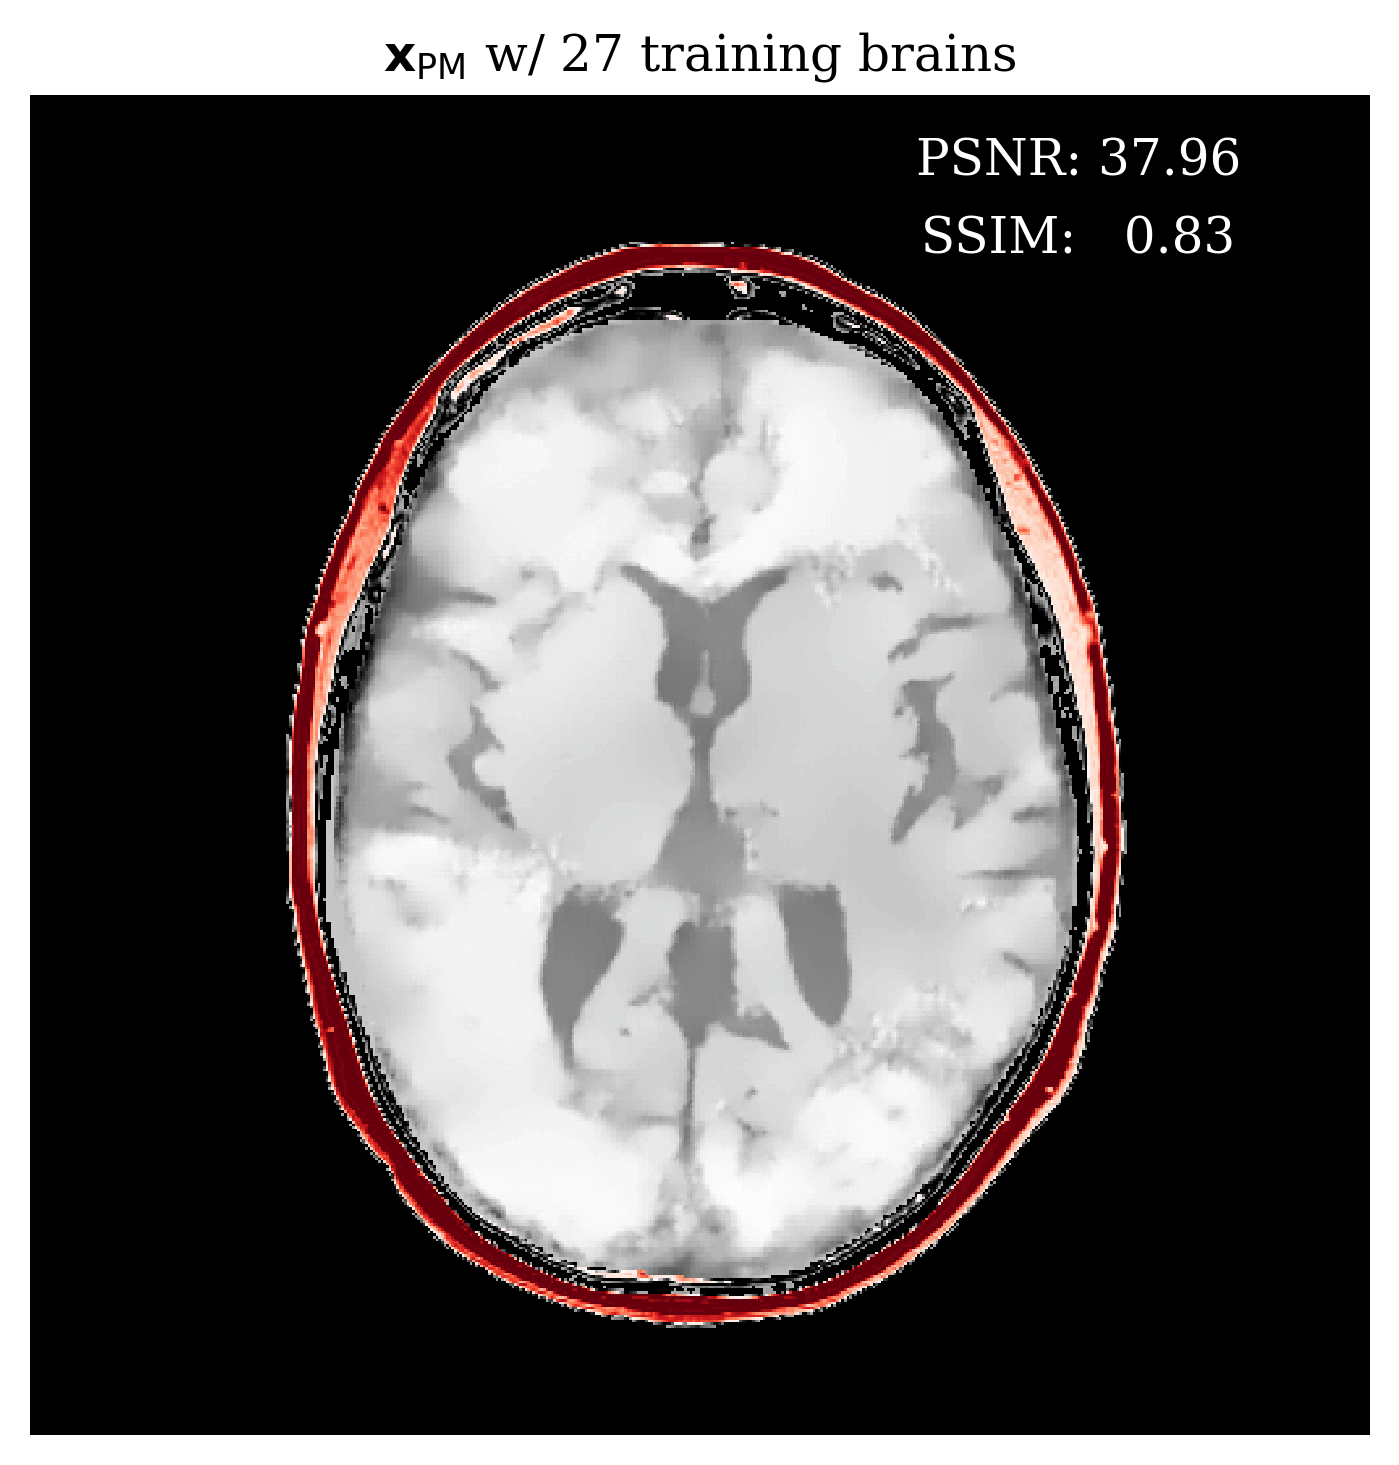

Since our method is Bayesian, its UQ results depend on how well it has learned the prior from training examples. In the case of conditional normalizing flows the prior is not explicitly accessible from the network since the network directly learns to sample the conditional distribution. Nonetheless, we would like to gain intuition on the effect of more training samples on the methods performance. In \figurereffig:trainingsize, we demonstrate the effect of increasing the training dataset size, on the posterior mean quality and on the UQ map that is produced. We observe from \figurereffig:trainingsize that as training samples increase, the posterior mean gets closer to the ground truth and that the UQ map becomes more contracted. These observations are similar to what happens when we increase the amount of observed data as explained in \sectionrefsec:uncertainty.

\subfigure

\subfigureUQ

\subfigureError

|